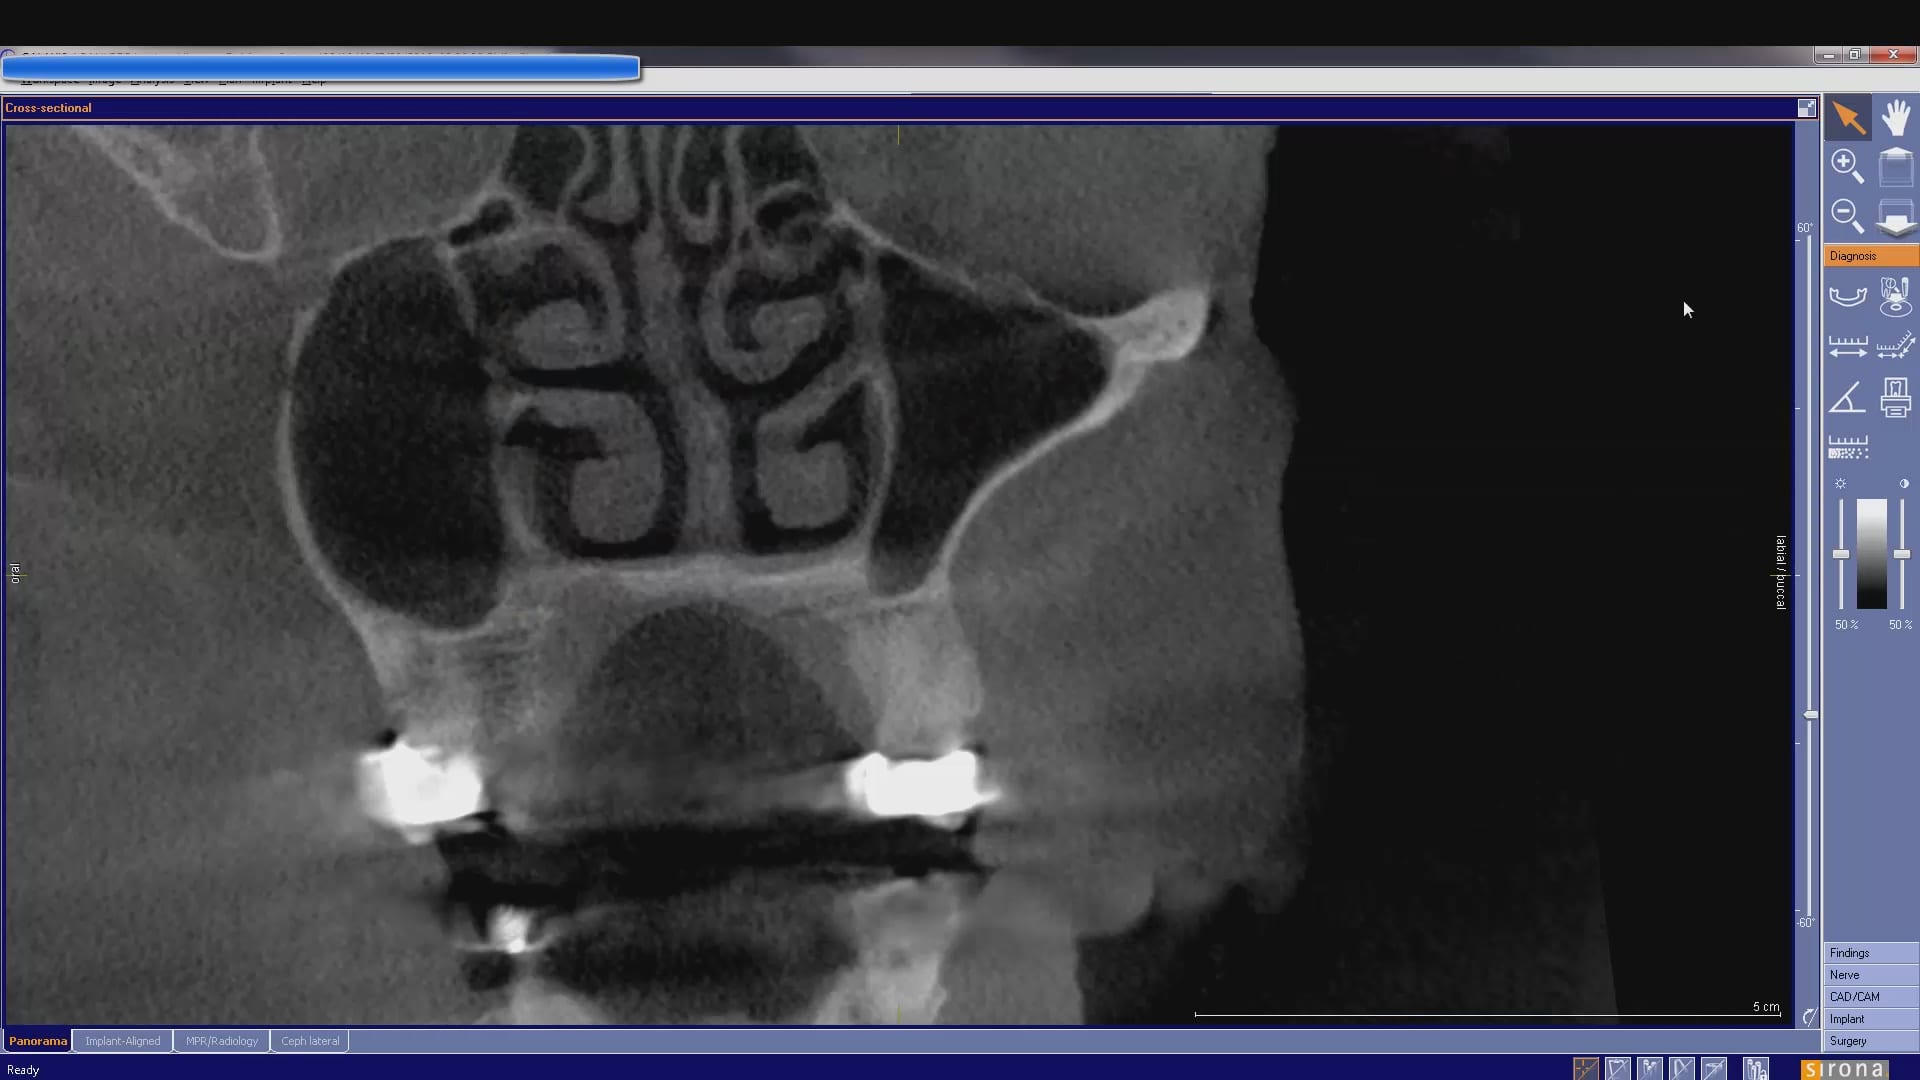

At CAD-Ray, we are big proponents of open architecture and the doctors control the flow of their patients’ digital data, whether it is a CT scan or an digital impression […]